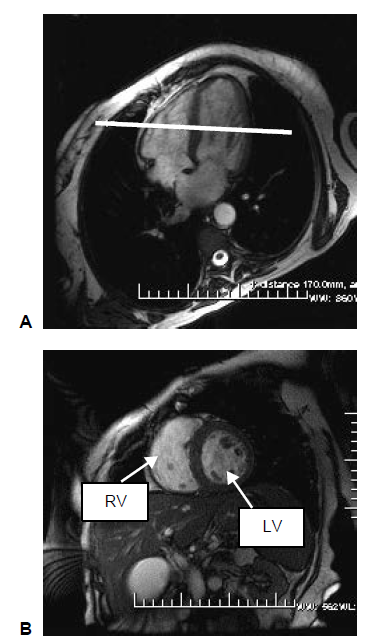

A complete short axis (SA) stack of balanced steady state free precession (bSSFP) cines covering the left ventricle (LV) and right ventricle (RV). A short-axis image stack typically consists of 10 image slices. Each cardiac cycle consists of 50 time frames (Petersen et al., 2015).

To acquire a short axis view, center perpendicular to the septum on the four-chamber long axis view (HLA). The resultant image will demonstrate the LV and RV in a nice circular shape.